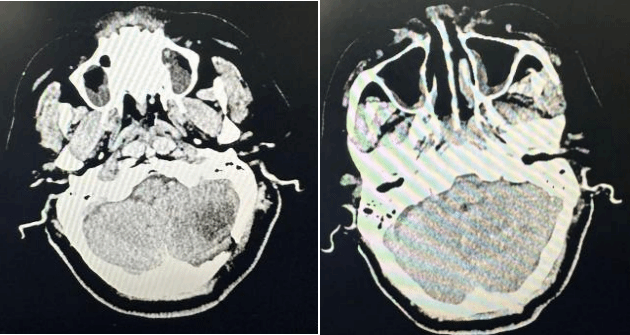

患者生命体征极不稳定,麻醉诱导和维持风险极高,袁浩峥医生麻醉团队凭借高超的技术与丰富的经验,平稳地将患者引入麻醉状态,使手术得以顺利开始。王举波副主任医师主刀、权瑜主治医师、高攀主治医师辅助,在手术室吴莉娜等配合下,手术历时近3小时,顺利为患者完成侧脑室前角穿刺、脑室外引流术、小脑血肿清除术。

术后CT